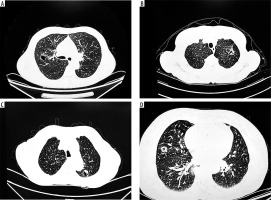

Cystic lung cancer presents with heterogeneous features on CT; however, key imaging characteristics suggestive of malignancy include irregular cyst wall thickness, internal septation, mural nodules, and uneven margins (Figure 3) [20]. In our study, we also incorporated the relationship between pulmonary nodules and surrounding tissues to explore imaging signs associated with malignancy. Malignant lung cancer cells are highly invasive, often resulting in irregular margins and the appearance of fine spiculations [21]. Consistent with previous findings by Si et al. [22], our results showed that the presence of a burr sign was an independent predictor of cystic lung cancer (p = 0.001, OR = 0.269). In the malignant transformation of pulmonary nodules, the growth of the lesion becomes unbalanced, leading to fibrous band formation [23]. Our data revealed a statistically significant association between the pleural indentation sign and malignant cystic nodules (p = 0.002, OR = 0.214). However, some studies [24] have questioned the diagnostic value of this sign in assessing the invasiveness of lung nodules. A study by Jung et al. [25] proposed that the imaging manifestations of cystic lung carcinoma are developmental, with a gradual increase in malignancy correlating with the progressive thickening of the capsule wall. Our findings partially align with this theory. Specifically, intracystic features such as the number of lumens (p = 0.034), wall smoothness (p = 0.022), homogeneity of wall thickness (p < 0.001), and the ground-glass opacity (GGO) sign (p < 0.001) were significantly associated with malignancy. Conversely, vascular penetration and lobulation were not significantly associated with GGO aggressiveness, possibly due to the smaller average size of the nodules and the relatively mild variation in growth across regions. In addition, intracystic septation and mural nodules were not statistically significant in our analysis, likely due to sample size limitations or confounding factors, highlighting the need for larger sample sizes and more refined statistical modelling in future studies.

Figure 3

A) Burr sign with vascular penetration, (B) separation is seen inside the cystic cavity, (C) ground glass shadow around the cystic cavity wall, and (D) thickening of the wall of the cystic cavity and visible wall nodules